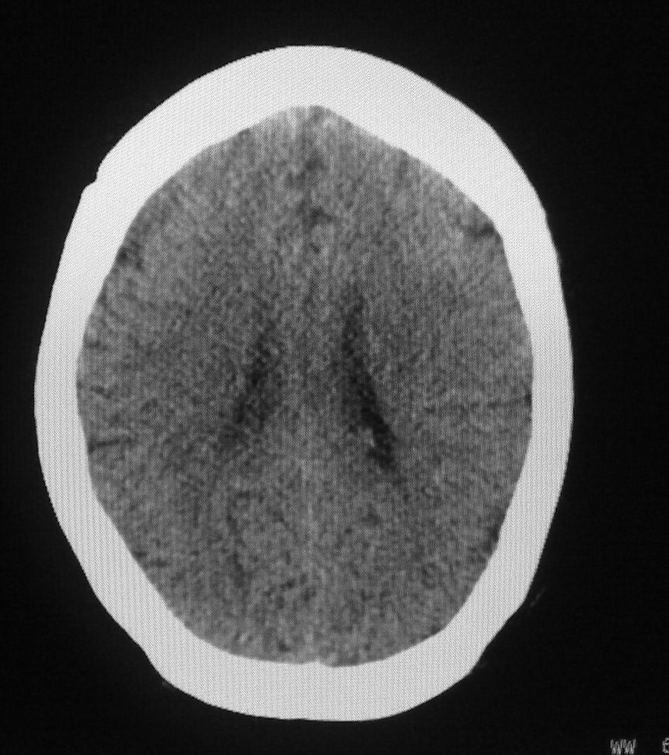

女,46岁,走路有时向一侧偏斜。是小脑萎缩吗?

小脑脑沟增多加深      为小脑萎缩引起的共济失调

小脑脑沟多于四条即为增多,又见加深,所以支持小脑萎缩。

从图像上看的确有轻度小脑萎缩征象,但患者才46岁,有外伤史吗?

小脑萎缩可能性大,建议mri检查。

小脑轻度萎缩